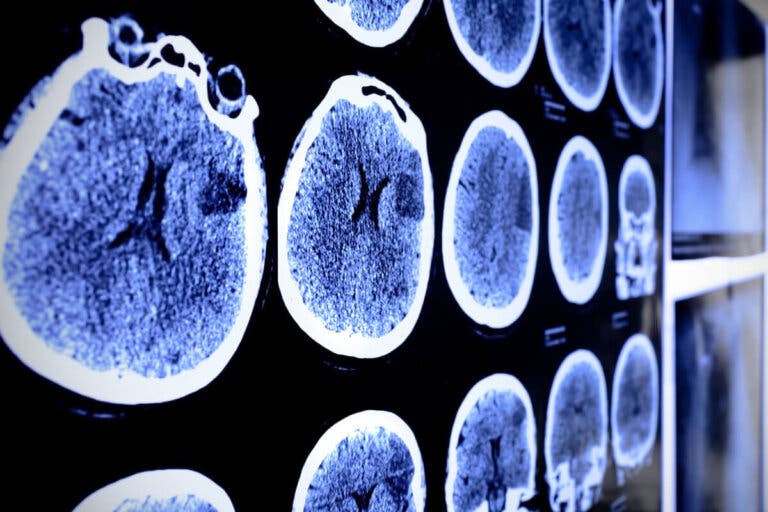

Pruebas de diagnóstico por imagen

El estudio imagenológico es vital para la identificación de las patologías tumorales a nivel del tejido cerebral. En general, la resonancia magnética (RM) es el más utilizado en el diagnóstico del astrocitoma.

La misma suele realizarse acompañada de medios de contraste que facilitan la ubicación del tumor y el establecimiento de un plan terapéutico.

De igual forma, se pueden emplear lo siguientes estudios:

- Espectroscopia.

- Tomografía computarizada (TC).

- Tomografía por emisión de positrones (TEP).

La biopsia por aguja forma parte crucial del diagnóstico definitivo de un tumor cerebral. La misma puede realizarse de forma guiada por resonancia magnética o por tomografía computarizada. La muestra obtenida debe ser enviada al especialista patólogo.